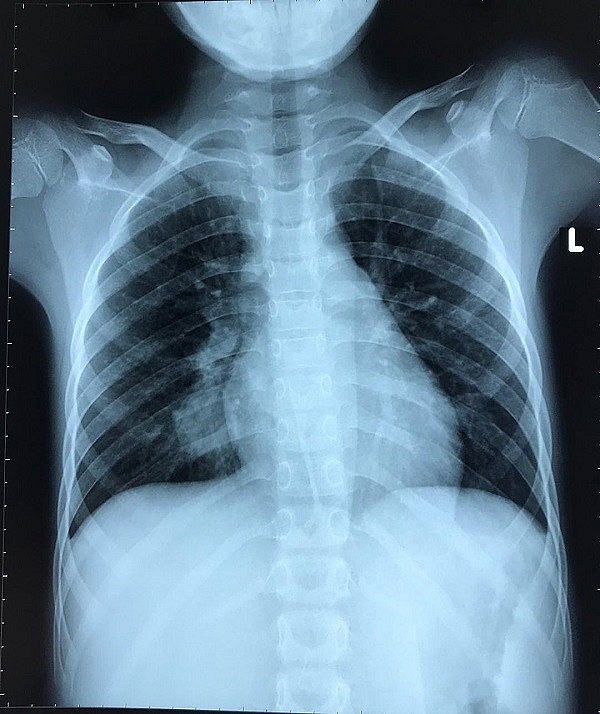

| Hình ảnh X quang phổi của bé trước khi phẫu thuật |

Qua hình ảnh chụp phim, nghi có khối u ở phổi phải, bé được chuyển sang bệnh viện Nhi đồng 2. Tại đây, bệnh nhi được CT Scan ngực, phát hiện túi phình động mạch phổi ở thùy dưới phổi phải, kích thước 20x18mm.